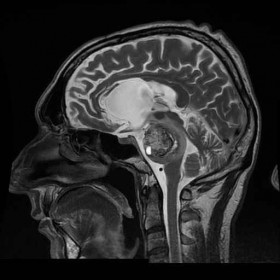

Essa affronta una patologia tumorale o vascolare benigna in sé (meningiomi, neurinomi, tumori vascolari), ma che si localizza in aree difficilmente raggiungibili con le tecniche classiche di neurochirurgia .

Si avvale di vie di accesso fino a pochi anni fa sconosciute, che si fanno strada attraverso le strutture ossee, nervose e vascolari della base del cranio, e che permettono di raggiungere la patologia senza porre alcuna trazione o compressione sulle strutture vitali del cervello.